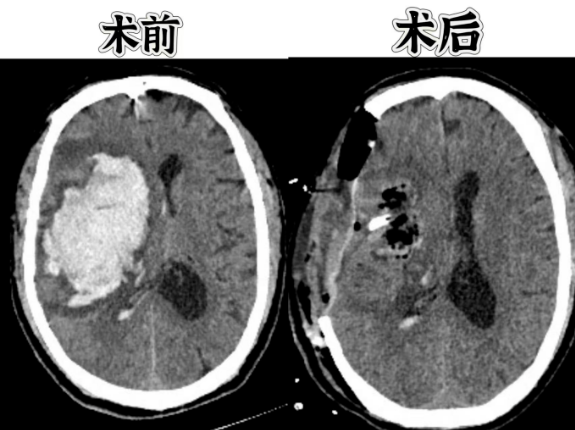

近日,济南南郊医院急诊科接收了一位危重患者。家属发现患者意识模糊、呼之不应,并伴有呕吐症状,立即拨打120急救电话。急诊科医护人员迅速响应,经CT检查发现患者左侧大脑半球大量出血,出血量约100毫升,确诊为脑疝、脑出血,病情十分危急。

时间就是生命!脑科郭晓宾主任和陈安平医生立即组织抢救团队,在最短时间内为患者实施了紧急开颅手术。手术团队精准清除了脑内血肿,实施了去骨瓣减压术,并置入颅内压监测传感器。术后CT显示血肿清除彻底,脑组织压迫得到有效缓解。